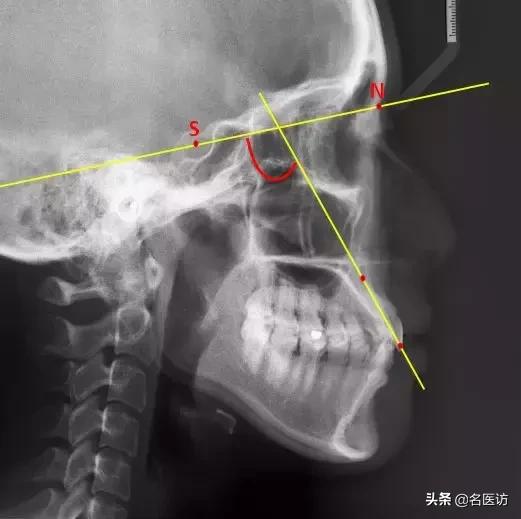

3、U1-SN

U1:上中切牙切缘点

反映上中切牙(俗称门牙)相对于颅底的倾斜度,角度越大,门牙越突,也就越可能出现龅牙的侧貌。